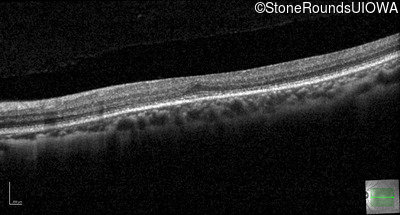

Optical Coherence Tomography - Right - 20/25 -3

Exemplar / OCT Stack

Optical Coherence Tomography - Left - 20/30 +2